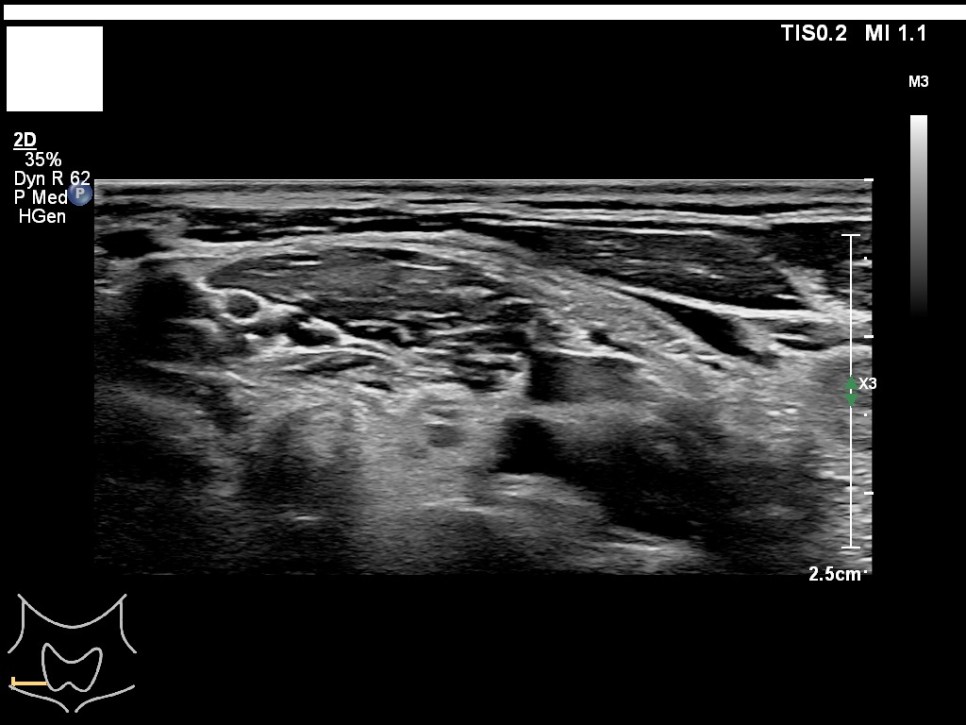

갑상선, 부갑상선 초음파 검사 급여 기준 1. 표준 영상의 범위 모든 영상에는 경부의 해부학적 위치(모식도나 문자)를 표기하여야 한다.

A) 병변이 없는 경우: 우엽 중부 가로 스캔, 우엽 중앙부 세로 스캔, 협부 가로 스캔, 좌엽 중부 가로 스캔, 좌엽 중앙부 세로 스캔, 우경부 림프절, 좌경부 림프절 나) 병변이 있는 경우: 병변이 없는 경우의 표준 영상과 함께 병변 부위에서 2개의 수직 관계 단면 영상(횡단/종단) 및 병변의 크기가 측정된 경우: 병변이 없는 경우의 표준 영상